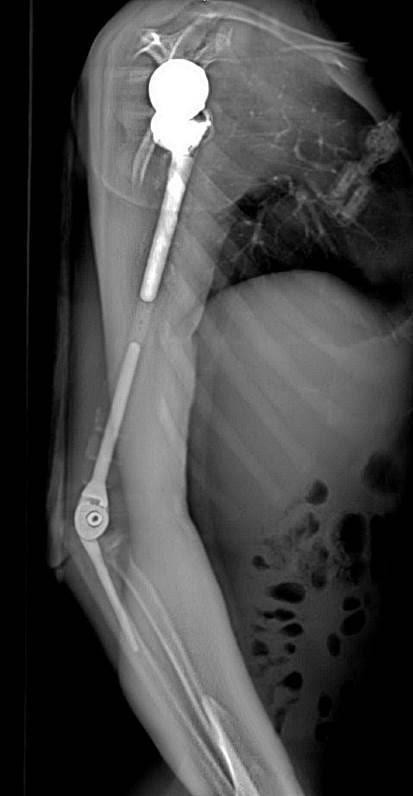

GS.TS.BS. Trần Trung Dũng - Giám đốc Trung tâm cho biết, đây là trường hợp tổn thương ung thư xương cánh tay hiếm gặp. “Khối u đã xâm lấn rộng toàn bộ ống tủy và phần mềm xung quanh, không còn khả năng cắt và bảo tồn một phần xương được nữa nên chúng tôi đã phải đưa ra một quyết định táo bạo. Đó là thực hiện phẫu thuật cắt bỏ toàn bộ xương cánh tay và khối u, đồng thời thay thế toàn bộ xương cánh tay bằng vật liệu nhân tạo dạng kết hợp để khắc phục nhược điểm của vật liệu kim loại” - GS.TS.BS. Trần Trung Dũng chia sẻ.

| Ảnh chụp X-quang tay phải của bệnh nhân sau khi phẫu thuật thay xương toàn bộ cánh tay |

Nhóm phẫu thuật đã lên kế hoạch sử dụng các công nghệ trong tái tạo xương hiện đại nhất hiện nay bao gồm tái tạo lại cấu trúc khớp vai, cấu trúc khớp khuỷu bằng vật liệu hợp kim titan.

Đặc biệt, đội ngũ bác sĩ của Trung tâm đã có một quyết định định táo bạo: không sử dụng hoàn toàn vật liệu kim loại mà chế tạo phần thân xương cánh tay sử dụng công nghệ in 3D vật liệu polyme sinh học (PEEK).

Vật liệu này do phòng nghiên cứu ứng dụng công nghệ in 3D của Đại học VinUni sản xuất, giúp kết nối phần khớp vai và khớp khuỷu với nhau, đồng thời phục hồi lại điểm bám của các gân cơ quanh cánh tay.